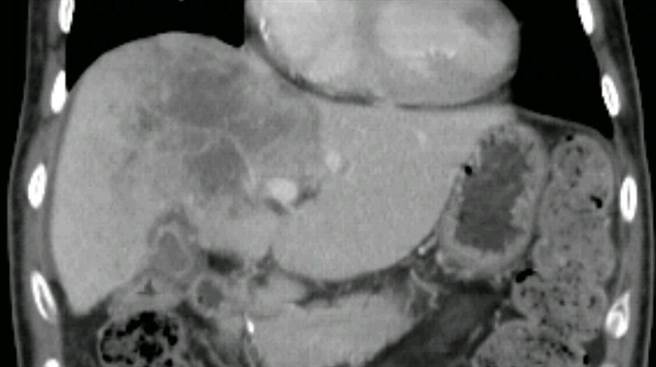

在精準醫療的時代,次世代定序(Next Generation Sequencing, NGS)幫助不少癌症病人獲得有效的治療方法,但彰化秀傳醫院病理科朱旆億主任表示,NGS檢測的成功與否,與病人的檢體品質有相當程度的關係。當癌症病人為癌症基因檢測向進行手術之醫院申請癌症檢體時,若當初開刀取得的癌症檢體量太少或癌症壞死組織太多,有部分病人是沒有辦法進行NGS檢測的。因此在準備進行癌症基因檢測前,務必要留意手術取得癌症檢體的品質及大小,並尋找專業基因檢測公司針對檢體腫瘤細胞進行刮取處理,才能確保檢測出精準的癌症基因資訊,真正受惠於精準醫學。

嚴重肝癌患者新福音!「肝動脈化學灌注」改善30人病況-生活-…

嚴重肝癌患者新福音!「肝動脈化學灌注」改善30人病況